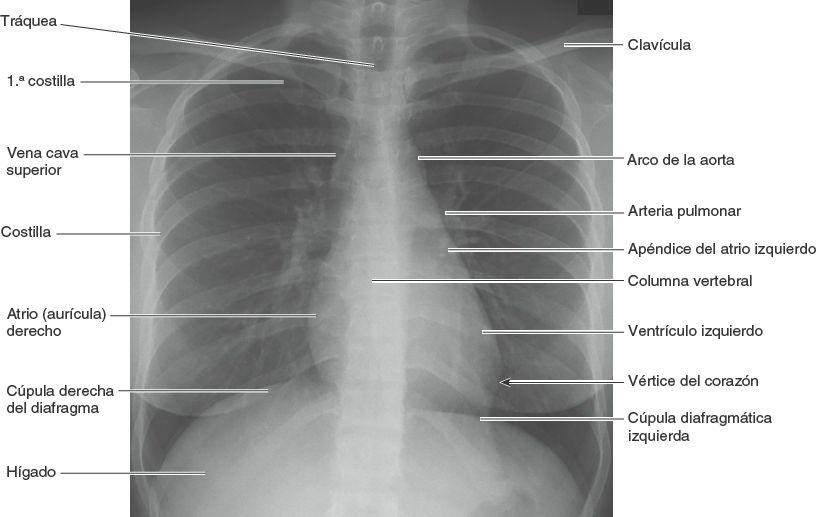

Los estudios radiográficos convencionales que no emplean técnicas especiales, tales como medios de contraste, se denominan clínicamente radiografías simples (fig. 1-49), aunque en la actualidad la mayoría de las imágenes se producen y visualizan digitalmente en monitores en vez de en placas radiográficas. En la exploración radiológica, un haz muy penetrante de rayos X transilumina al paciente y muestra los tejidos con masas de diferentes densidades como imágenes de distinta intensidad (áreas con luces y sombras relativas) en la placa radiográfica o en el monitor (fig. 1-50). Un tejido u órgano cuya masa sea relativamente densa (ej. el hueso compacto) absorbe o refleja los rayos X más que otro tejido menos denso (ej. el hueso esponjoso). Por lo tanto, un tejido u órgano denso produce un área algo transparente en la radiografía, o un área brillante en el monitor, porque hay menos cantidad de rayos X que alcanzan la placa o el detector. Una sustancia densa es radiopaca, mientras que otra de menos densidad es radiotransparente.

Muchos principios que son aplicables a la formación de una sombra lo son también a la radiografía convencional. Así, al proyectar la sombra de la mano sobre una pared, cuanto más cerca de esta se halle la mano tanto más nítida será la forma de la sombra; al apartar la mano de la pared y acercarla a la fuente de luz, la sombra se ampliará. Las radiografías se realizan con la parte del paciente a estudiar próxima a la placa radiográfica o al detector, para maximizar la claridad de la imagen y minimizar los artefactos por aumento. En la nomenclatura radiológica básica, la proyección posteroanterior (PA) se refiere a una radiografía en la cual los rayos X atraviesan al paciente desde la parte posterior (P) hacia la anterior (A); el tubo de rayos X se halla detrás del paciente, y la placa radiográfica o el detector delante (fig. 1-51 A). En una radiografía en proyección anteroposterior (AP) ocurre lo contrario.

Las radiografías se visualizan con una orientación estándar independiente de la proyección radiográfica. Para la mayor parte del cuerpo, incluyendo la cabeza y el tronco, la cintura escapular y los brazos debajo de los codos, y hasta las piernas, incluyendo los tobillos, todas las radiografías PA, AP y oblicuas se contemplan como si el observador y el paciente se hallaran uno frente al otro (el lado derecho del paciente se halla frente al lado izquierdo del observador); esto se denomina vista anteroposterior (AP). Como se muestra en la figura 1-49, una radiografía de tórax PA se presenta con la derecha del paciente hacia la izquierda del observador y la orientación sería la misma al ver una radiografía de tórax AP. Para las muñecas, manos y pies, las radiografías se ven como si estuviera viendo sus propias muñecas, manos o pies. En las radiografías laterales se colocan letras radiopacas (D, derecho; I, izquierdo) para indicar el lado más próximo a la placa radiográfica o al detector, y la imagen se visualiza en la misma dirección en que se proyectó el haz de rayos (fig. 1-51 B).